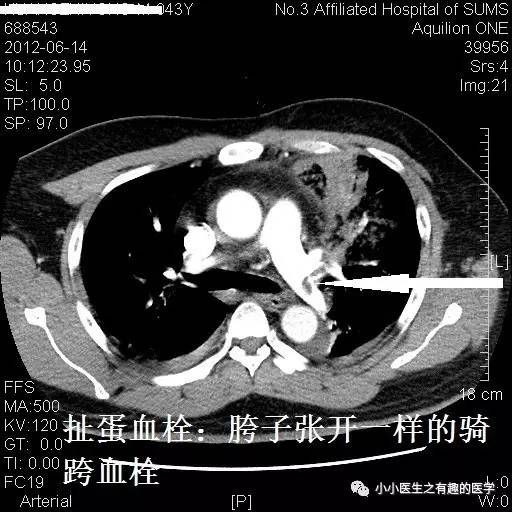

血栓太小了?来几个大的给你看看。首先,看看大扯蛋血栓。医学上,有种血栓叫骑跨血栓,很危险,骑跨:听着很拗口,也不形象,叫扯蛋血栓更形象。

部分学者认为骑跨血栓风险高,即使血流动力学稳定(无休克、血压下降等)也应该给予强有力的治疗:外科手术取栓、介入取栓、溶栓治疗,迅速溶解血栓恢复肺循环血流。真是扯着蛋了。

广州呼研所报道的一例:扯蛋血栓。

入院后给予伊诺肝素钠皮下注射,第2天患者气促较前加重。体检:呼吸27次/分,Sp02:90%(吸氧4 L/min),血压103/62 mmHg。家属签署同意书后,给予重组人组织纤维蛋白溶酶原激活物50mg,静脉滴注2 小时,溶栓后患者气促缓解。

治疗后复查,血栓基本溶解。